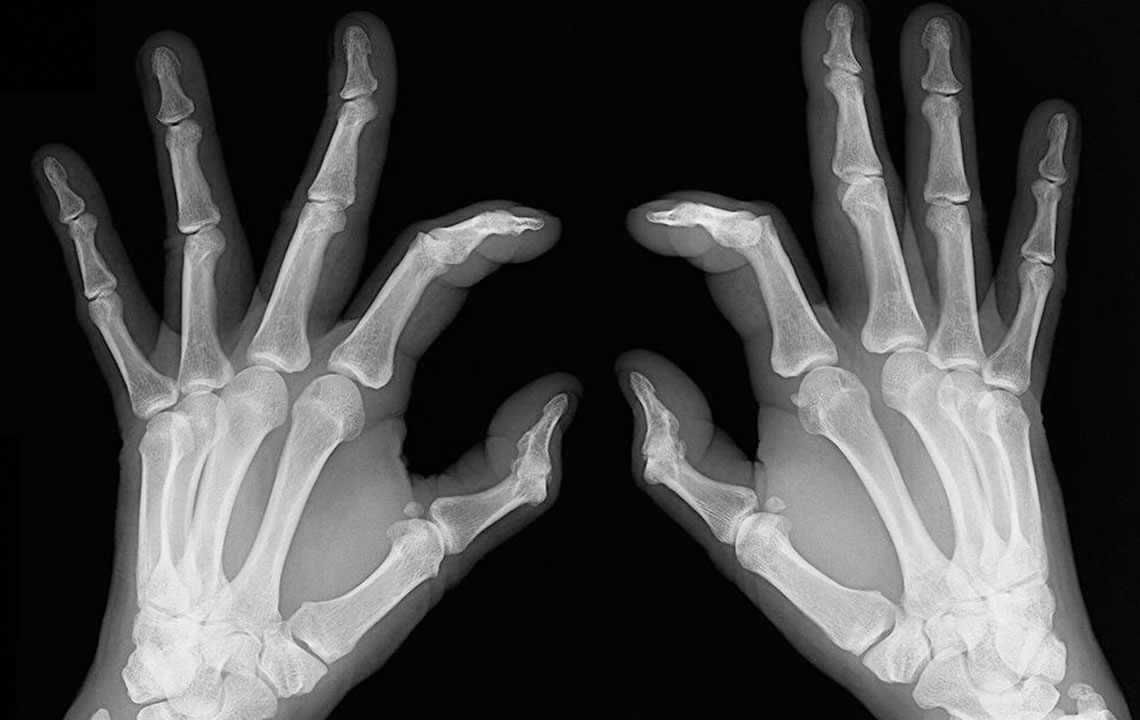

The most shared and evident similarity that rheumatoid arthritis and lupus share is joint pain. However, the levels of inflammation and swelling of joints may vary between these conditions. Joint pain is also a common symptom of patients diagnosed with either rheumatoid arthritis and lupus. Also, the joints can become warmer and tender, though this is a more prominent symptom of rheumatoid arthritis.

It is these similarities that cause a lot of confusion with the diagnosis of rheumatoid arthritis and lupus. There are several times when patients are diagnosed with rheumatoid arthritis when they actually have lupus. This usually happens in the early stages of the disorder. As the condition progresses, the difference becomes evident; rheumatoid arthritis causes bone deformity and erosion while lupus rarely leads to bone erosion.